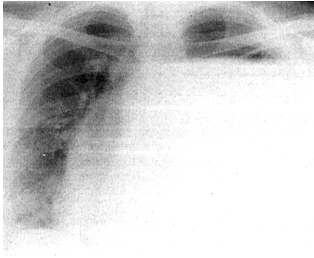

Slika 1. Inicijalna radiografija grudnog koša

Radiografija grudnog koša (Slika1) ukazuje na hidropneumotoraks

levo, sa infraklavikularno prisutnim hidroaeričnim nivoom. Srčana

senka potisnuta put desno. Sve laboratorijske i biohemijske analize